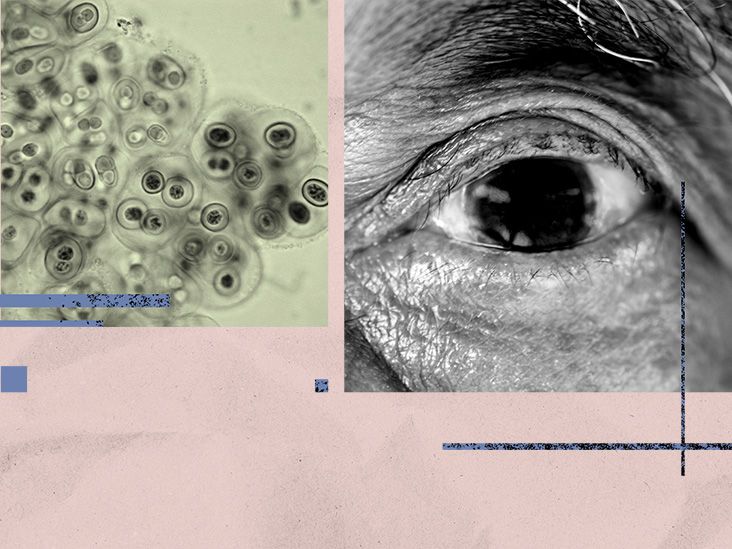

| Risk factors for geographic atrophy |

| Risk factors for geographic atrophy, include age, genetics, health conditions, and lifestyle influences. Learn more. |